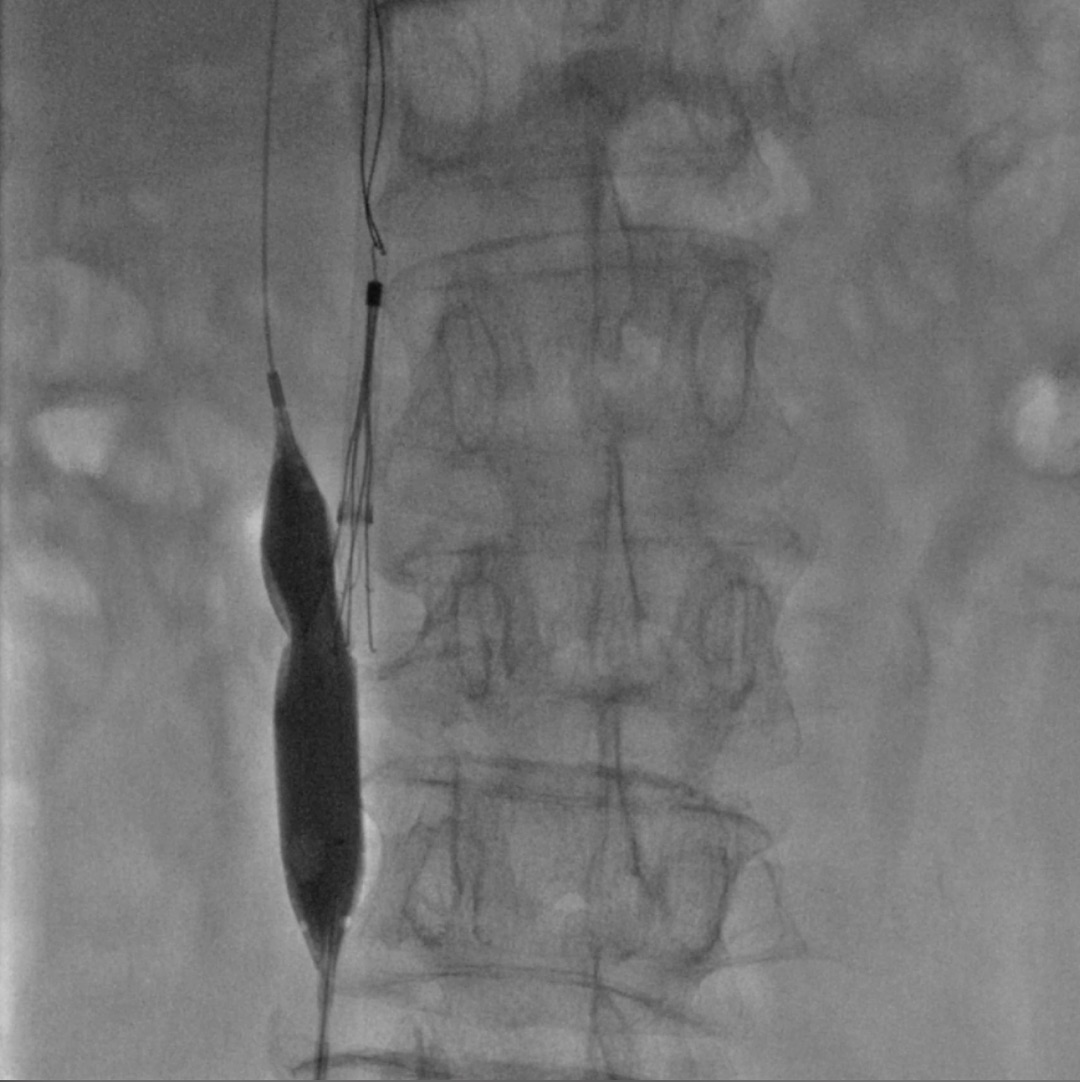

手术对象为66岁骨盆骨折患者,外科术前因下肢深静脉血栓形成,下腔静脉置入临时滤器。骨盆骨折修复术后,血栓因为各种原因并未完全吸收,错过了滤器取出的最佳时间,若滤器长期滞留在病人体内,会造成一定程度的不良影响,遂决定取出滤器。放射科介入诊疗组,针对这一病例进行了术前充分的讨论,拟定了几种滤器取出手术的预案。手术时,放射科导管室主任张凯、李彩霞主任医师、见文成副主任医师台下指导,台上孙向阳主治医生、马晓晨住院医生和谢阳住院医生密切协作,创新性地应用球囊切割技术及导丝切割技术,历经一个多小时的努力奋战,终于将嵌入血管内膜的滤器取出,圆满完成手术。术后患者安返病房。

深静脉血栓患者外科手术,存在巨大潜在风险,目前下腔静脉滤器置入对于致命性肺动脉栓塞的预防作用已经得到医学界广泛的认同和接受。由于永久留置的下腔静脉滤器可能引起下腔静脉闭塞、血栓形成及复发性深静脉血栓形成等并发症,可回收式腔静脉滤器可在一定时限内被取出,从而避免了长期留置造成的不良反应。但与此同时,可回收腔静脉滤器置入时可能出现倾斜、回收钩贴壁等情况,在体内留置期间因血管壁组织增生可能造成滤器与血管壁融合,从而降低了滤器回收的成功率。近年来,采用常规技术无法成功取出的可回收腔静脉滤器的情况逐渐增多,齐鲁医院的球囊切割技术及导丝切割技术为疑难性下腔静脉滤器回收处理提供了重要的临床探索。(王文斐 刘艳)